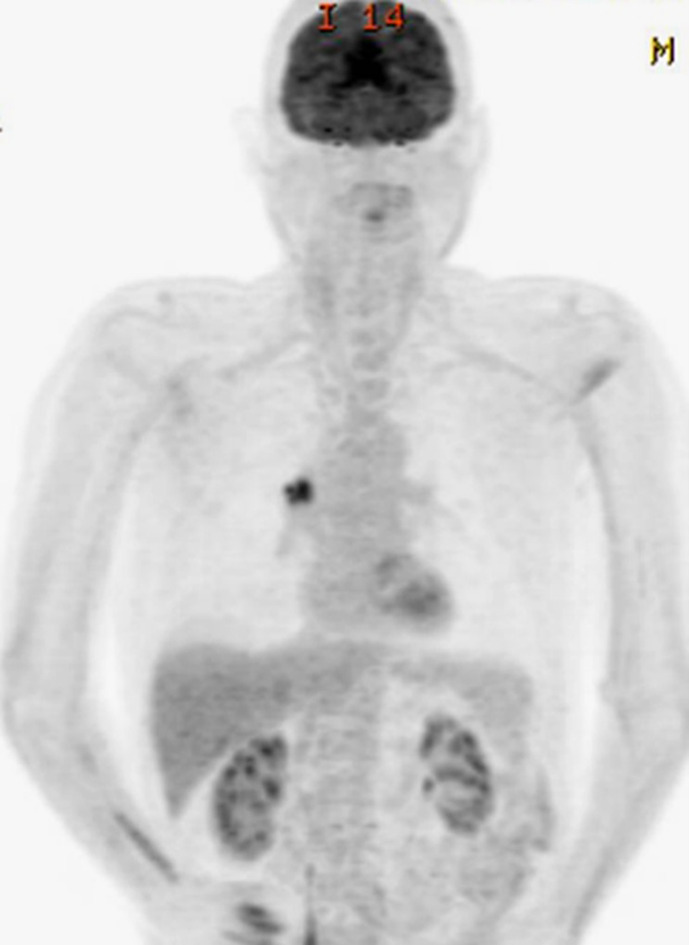

Case presentation: The patient initially presented with incidental bilateral disc swelling but was asymptomatic, with preserved visual function. Initial investigations, including orbito-cranial imaging, lumbar puncture, temporal artery ultrasound, and serological testing, were inconclusive. Six weeks later, the patient had persistent disc swelling with compromised bilateral visual function and was commenced on oral steroids. Further diagnostic workup identified paraneoplastic antibodies (anti-CV2/CRMP-5 and anti-Hu) and PET scan findings consistent with a nodular SCLC. Following biopsy confirmation, the patient underwent carboplatin and etoposide chemotherapy, followed by radiotherapy. Initial oral steroids, prior to cancer treatment, resulted in resolution of optic disc swelling and stabilization of visual function.